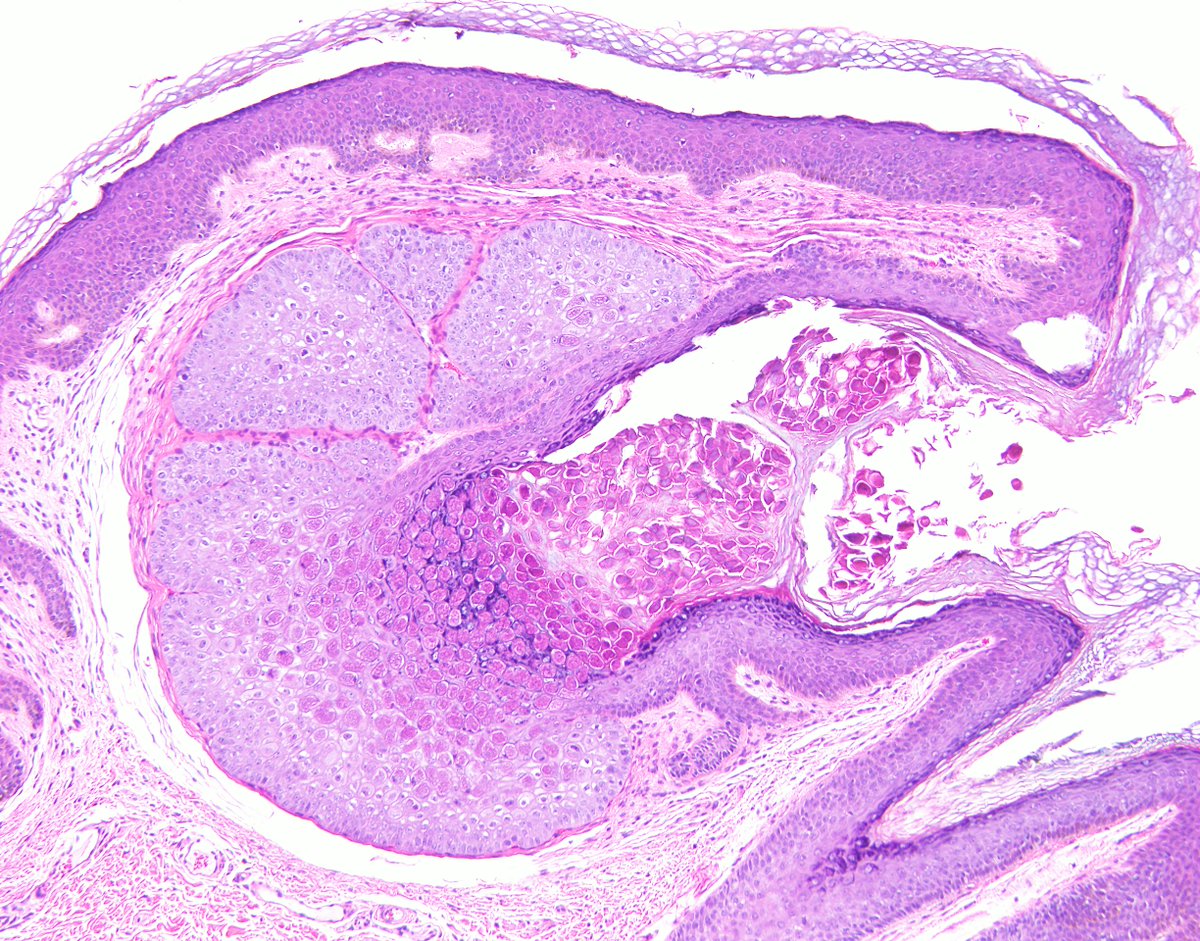

"BOW TIE". Papillary thyroid carcinoma. #FNA Thyroid. #Entpath #endopath #pathology #pathtwitter #PathTweetAward @MSWPathology @MyCytopathology @SamKhader